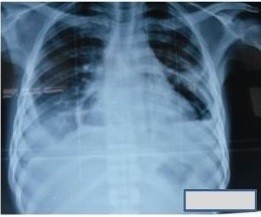

Introducción: el neumopericardio es una entidad potencialmente mortal y dependiendo del factor etiológico presenta formas clínicas variadas. En pacientes con taponamiento cardiaco debe realizarse inmediatamente punción y colocación de un drenaje pericárdico. Tiene mal pronóstico, con una mortalidad del 90%. Objetivo: resaltar el papel que adquiere la radiografía de tórax en cuanto a capacidad diagnóstica. Presentación de casos: Se muestran tres casos en escenarios sanitarios diferentes. Dos de ellos de nacionalidad angolana y el tercero atendido en el Hospital Pediátrico Provincial de Sancti Spíritus, Cuba: Conclusiones: constituye una complicación grave con múltiples etiologías y su incidencia es baja. La radiografía de tórax es el medio diagnóstico fundamental, con mejor capacidad que la ecocardiografía para definir su gravedad y posibles causas.